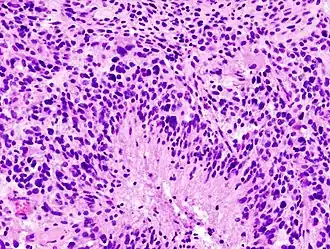

.jpg)

- Пилоцитарная астроцитома (I степень злокачественности) — доброкачественная опухоль с четкими границами, растет медленно. Чаще встречается у детей. В основном локализируется в мозжечке, стволе мозга и зрительных нервах.

- Фибриллярная астроцитома (II степень злокачественности) — опухоль без четких границ, растет медленно. Встречается у больных 20-30 лет.

- Анапластическая астроцитома (III степень злокачественности) — злокачественная опухоль без четких границ, растет быстро, прорастает в мозговую ткань. Возраст у больных 30—50 лет, чаще болеют мужчины.

- Глиобластома (IV степень злокачественности) — наиболее злокачественная опухоль без четких границ, растет очень быстро, прорастает в мозговую ткань. Возраст у больных 40—70 лет, чаще болеют мужчины[4].